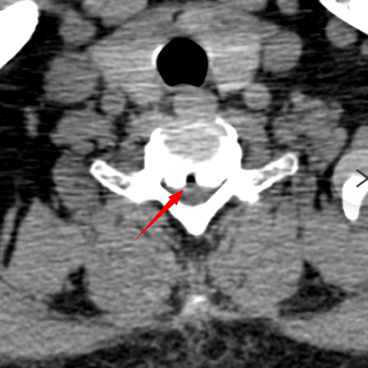

颈椎CT显示C6/7平面增生的骨赘占据椎管,压迫脊髓